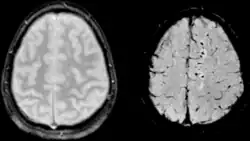

Vergleich einer axonalen Verletzung aufgenommen mit konventioneller GRE (links) und mit SWI (rechts) bei 1.5 T

Vergleich einer Hirnblutung aufgenommen mit konventioneller GRE (links) und mit SWI (rechts) bei 1.5 T